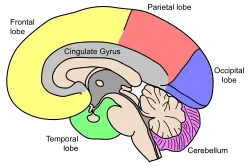

| Lobes of the human brain |

Advances in MRI technology have provided the ability to see the brain structure in great detail in an easy, non-invasive manner in vivo. Bartzokis et al., has noted that there is a decrease in grey matter volume between adulthood and old age, whereas white matter volume was found to increase from age 19–40, and decline after this age.[13] Studies using Voxel-based morphometry have identified areas such as the insula and superior parietal gyri as being especially vulnerable to age-related losses in grey matter of older adults.[13] Sowell et al., reported that the first 6 decades of an individual's life were correlated with the most rapid decreases in grey matter density, and this occurred over dorsal, frontal, and parietal lobes on both interhemispheric and lateral brain surfaces. It is also worth noting that areas such as the cingulate gyrus, and occipital cortex surrounding the calcarine sulcus appear exempt from this decrease in grey matter density over time.[13] Age effects on grey matter density in the posterior temporal cortex appear more predominantly in the left versus right hemisphere, and were confined to posterior language cortices. Certain language functions such as word retrieval and production were found to be located to more anterior language cortices, and deteriorate as a function of age. Sowell et al., also reported that these anterior language cortices were found to mature and decline earlier than the more posterior language cortices.[13] It has also been found that the width of sulcus not only increases with age,[14] but also with cognitive decline in the elderly.[15]

Age-related decrease in gray matter volume was the largest contribution to changes in brain volume. Moreover, neuronal density appears to decrease, white matter microstructure gets altered and energy metabolism in the cerebellum gets altered.[16] General cortical atrophy occurs in aging and e.g. the caudate nucleus volume appears to decrease.[17]